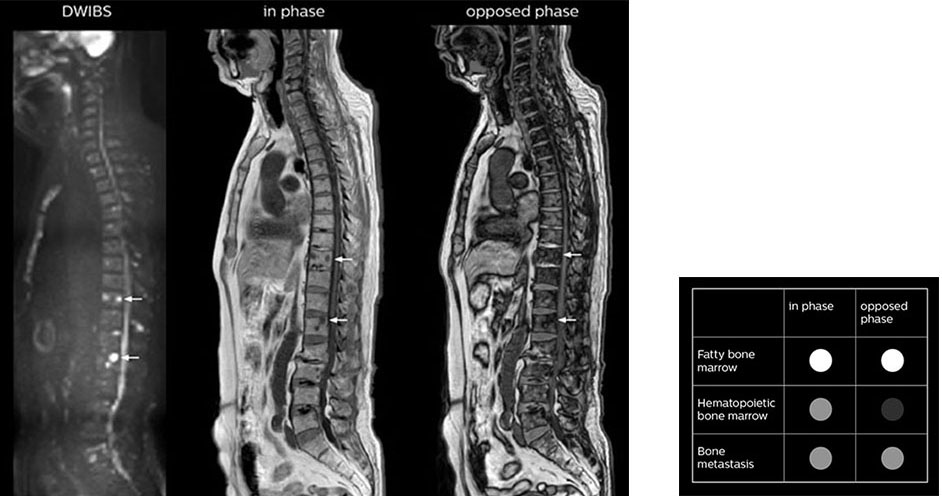

Kawasaki Sawai Hospital’s whole body protocol also includes an mDIXON FFE sequence. Because mDIXON provides images for four contrast types – water only, fat only, in-phase and out-of-phase – from a single acquisition, it is useful in many ways.

“mDIXON FFE allows us to quickly get information we need to assess the presence of fat. That gives us more information when we need to diagnose bone lesions, and when we are asked to judge fat-containing lesions such as hepatocellular or renal carcinoma,” Dr. Nobusawa says.

“The mDIXON fat images can help us to differentiate fatty bone marrow from bone lesions. This is especially useful in elderly people, who tend to have fattier bone marrow. The water images provide a high signal-to-noise ratio in the intestinal canal, which is valuable for visualizing lesions in the colon,” he says.

“In-phase and out-phase sagittal T1-weighted FFE images help us to visualize and further characterize bone lesions such as metastasis and bone-marrow hyperplasia that have high signal on DWI. These images are also used throughout radiotherapy, to monitor changes in the fatty bone marrow.”